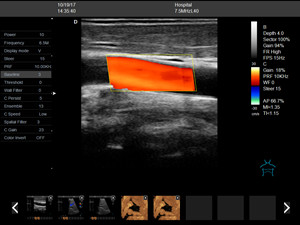

Name : Obstetric Urology Gynecology Ultrasound

Mode : B, 2B, B/M, B/C, CFM, PDI, PW

B&W mode: B, 2B, B/M, B/C

Color Doppler mode: CFM, PDI, PW

Triplex: Real-time simultaneous 2D, Doppler & CFM

Duplex: Real-time simultaneous 2D, Doppler

15 Inch Color Doppler Ultrasound Scanner Obstetric Urology Gynecology Images |